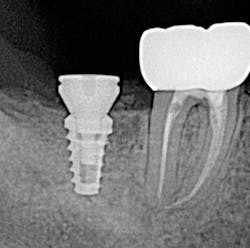

The old saying “you don’t know what you don't know” holds especially true in regard to 3-D radiology. You simply cannot gain the same amount of information from 2-D images. My main use for CBCT in the general dentistry practice is dental implant planning. In order to feel confident placing dental implants, I need this technology. I am able to identify cases that are appropriate for my skill level, as well as cases that are more difficult and should be referred. Whether a case will be tricky is not always obvious from a 2-D image and clinical exam. I also have not found a situation where less information was more beneficial than more information. I have never thought to myself, “I wish I didn’t have a 3-D scan of this patient.” Conversely, there were many times before buying my CBCT when I wished I had more than just a 2-D periapical (PA) or pan. The case shown in figures 1, 2, and 3 illustrates how the additional information CBCT provides aids in planning and placing dental implants.

Figure 3 tells a more complete story. The patient has a significant lingual concavity. I was unable to palpate the concavity clinically to realize its full extent. The 3-D image allows accurate measurement to the inferior alveolar nerve (IAN) and lingual concavity. It allows me to plan and place an implant of the appropriate length to avoid perforation of the lingual plate, which could lead to serious surgical complications.